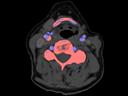

The question is: What makes True Dual Energy stand out? Look for these three criteria: crisp images with the option for even sharper contrast and significant artifact reduction; no extra dose in either Single Source or Dual Source Dual Energy scans, and a broad applicability for virtually all clinical questions and patients.

Discover Dual Energy (DE) spectral imaging. It’s the difference between images and answers. Visualization and characterization. Qualification and quantification. Built into all of our CT scanners, it delivers powerful performance, incredible versatility for your entire patient population, and exceptional ease-of-use – all while integrating seamlessly with your current workflow.